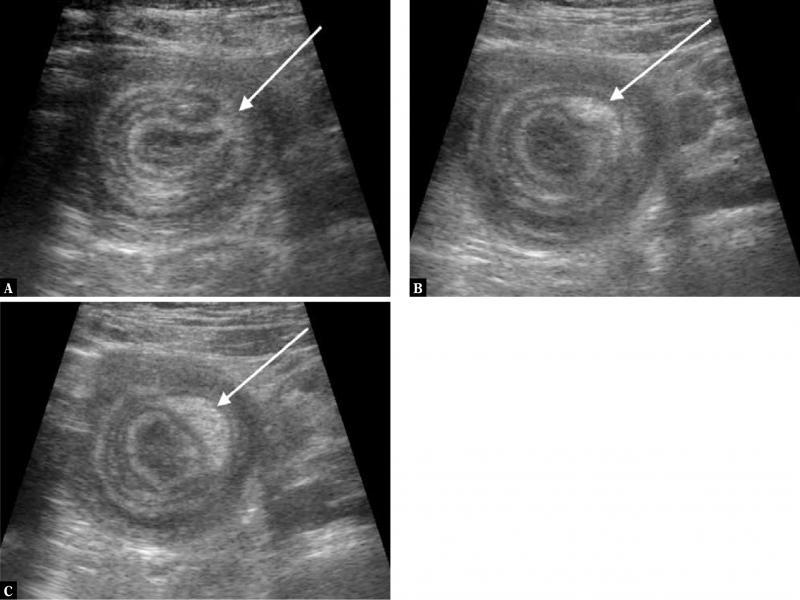

Fig. 3.

Ultrasound image in the longitudinal plane showing the pseudokidney appearance of the lesion with the hyperechoic mesentery (solid arrow) located eccentrically to the central limb (dashed arrow) of the intussusceptum